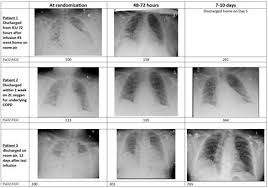

Rlf 100 Helps In Rapid Recovery From Respiratory Failure In Covid 19